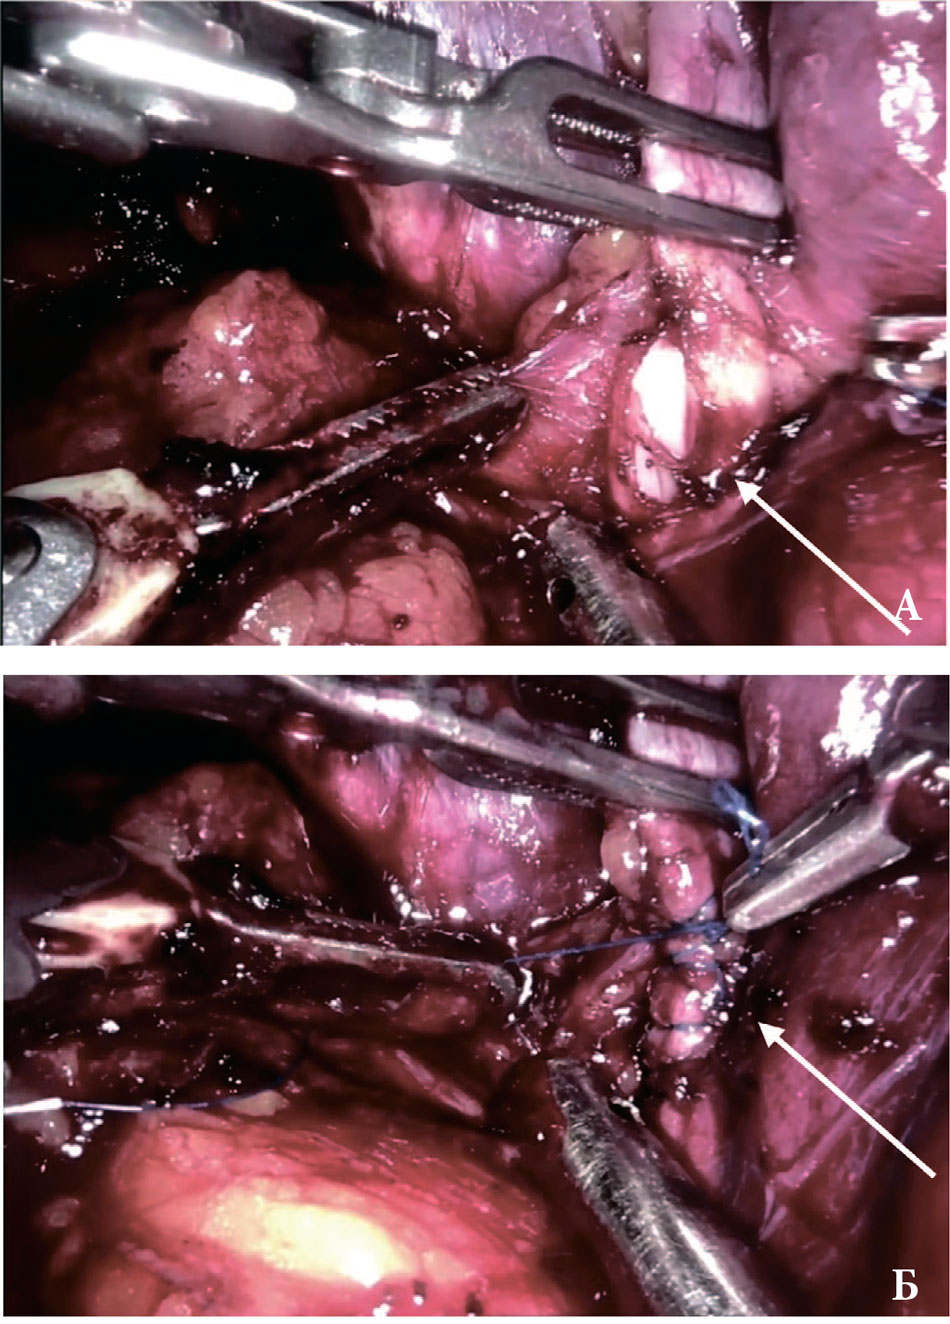

Подобные инциденты могут быть предотвращены путем использования более современного оборудования с системами контроля температуры и автоматического отключения, а также повышением квалификации медицинского персонала в плане работы с электрохирургическими инструментами. Необходимо также помнить о важности адекватного охлаждения тканей для предотвращения термического повреждения. Во всех случаях интраоперационного повреждения подвздошных сосудов была выполнена первичная хирургическая коррекция – ушивание дефектов сосудистой стенки. Ключевым моментом успешного восстановления целостности сосуда и минимизации кровопотери является тщательная мобилизация поврежденного участка с последующим временным пережатием сосуда для прекращения кровотечения. Это позволяет хирургу работать в условиях хорошего обзора и точно восстановить целостность сосудистой стенки. Пережатие осуществляется специальными зажимами, выбор которых зависит от локализации и характера повреждения. При ятрогении подвздошных вен временный гемостаз до восстановления целостности сосудов может быть достигнут повышением внутрибрюшного давления посредством создания пневмоперитонеума до 20–25 мм рт. ст. Это приводит к компрессии сосудов и снижению кровотечения. Однако следует помнить, что длительное повышение абдоминального давления может привести к негативным последствиям, таким как гипоперфузия внутренних органов. Поэтому этот метод должен использоваться только как временная мера до окончательного ушивания поврежденного сосуда. Таким образом, интраоперационные повреждения подвздошных сосудов при РПЭ, хотя и редки, требуют высокой квалификации хирурга, совершенствования хирургической техники, использования современного оборудования и тщательного планирования операции. Непрерывное совершенствование техники и технологий, а также анализ осложнений, позволят снизить риск подобных инцидентов и повысить безопасность роботизированной радикальной простатэктомии (рис. 3).

Рис. 3. Эндоскопическая картина травмы правой наружной подвздошной вены во время РПЭ: A – дефект в сосуде, указан стрелкой; B – вид ушитого дефекта, указан стрелкой

Fig. 3. Endoscopic picture of an injury to the right external iliac vein during RPE: A – the defect in the vessel, indicated by the arrow; B – the defect of the vessel after its suturing, indicated by the arrow